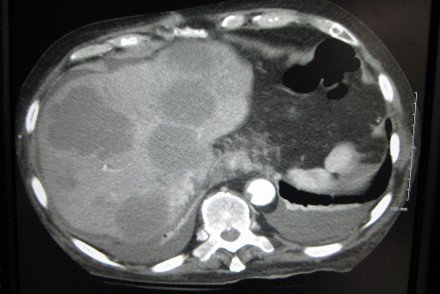

Heterogeneous mass measuring 13.3 x 11.1 x 9.7 cm, seen involving segment VIII and segment V in the right hepatic lobe, with hyperdense subsapsular hematoma at corresponding lateral hepatic surface and free intra-peritoneal hemorrhage.

Solitary cystic liver lesion with low attenuation center and peripheral thick enhancing wall.

CT Findings are consistent with amebic liver abscess.

Solitary cystic liver lesion with low attenuation center and peripheral thick enhancing wall.

CT Findings are consistent with amebic liver abscess.